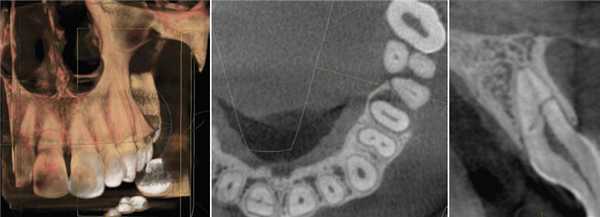

Фото 4: Периапикальная киста в переднем сегменте нижней челюсти

А: 3D изображение, показывающее большую кистозную полость

B: Изображение секционного распила, показывающее утрату кортикальной пластинки

C: Аксиальный вид, демонстрирующий утрату кортикальной пластинки с лабиальной стороны и интактную пластинку с лингвальной.

Фото 5: Хронические периапикальные абсцессы около первого правого нижнего моляра

Фото 6: Поражение периодонтальных тканей около левого верхнего второго моляра

Система индексов КЛКТ состоит из 6 ступеней (0-5), исходящих из определения самого большого размера повреждения в каком либо из измерений, и принятие в расчет расширение и разрушение кортикальной кости.